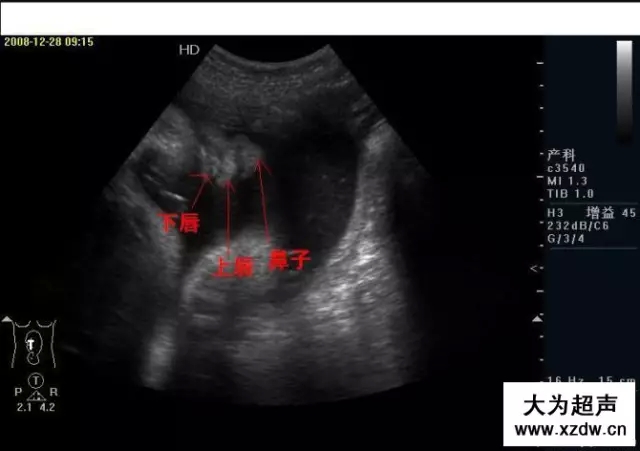

產(chǎn)科超聲正常圖片